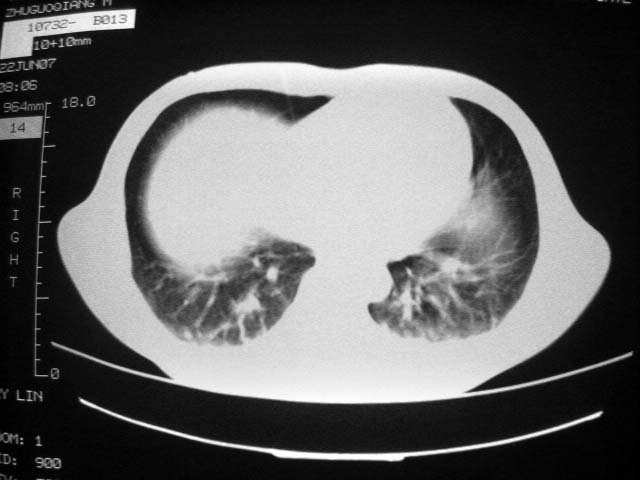

从ct7988c 至今未用任何抗生素及抗痨药,维持保肝治疗。患者低热、咳血渐消失。

07年6月22号复查

前几次大家认为是转移癌,但此次复查病灶却明显吸收好转,不支持诊断。请大家讨论。[emb10]

bu不可思议,前三次都怀疑转移,但从这次的片子看仍有结节,就是比原来小

双侧继发性肺结核伴两肺播散灶.双侧胸腔少量积液

近2个月病灶变化较大,应是感染性病变,首先考虑金黄色葡萄球菌感染。

根据前后片比较应该考虑迁徙性肺脓肿,回帖相差甚远是因为前后片变化太大出乎大家意料之外,这就是影象诊断要结合临床复查对比的必要性,

回顾既往片,病变明显吸收,缩小,未经治疗,不支持肺转移瘤,可能为肺结节病或韦格氏肉芽肿